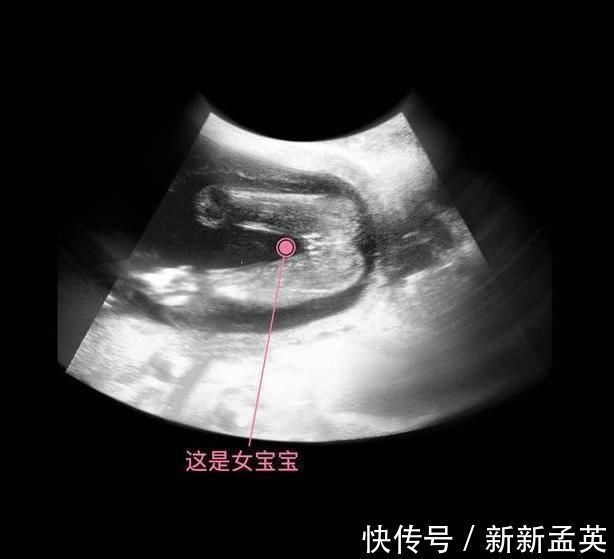

其实从孕9周开始,胎儿的性别就开始分化,孕17周,B超扫描清晰可见胎儿的性别,不过也有的宝宝因为胎位的原因,或者脐带遮挡,让医生产生了误判,男女会出现翻盘的可能呢。